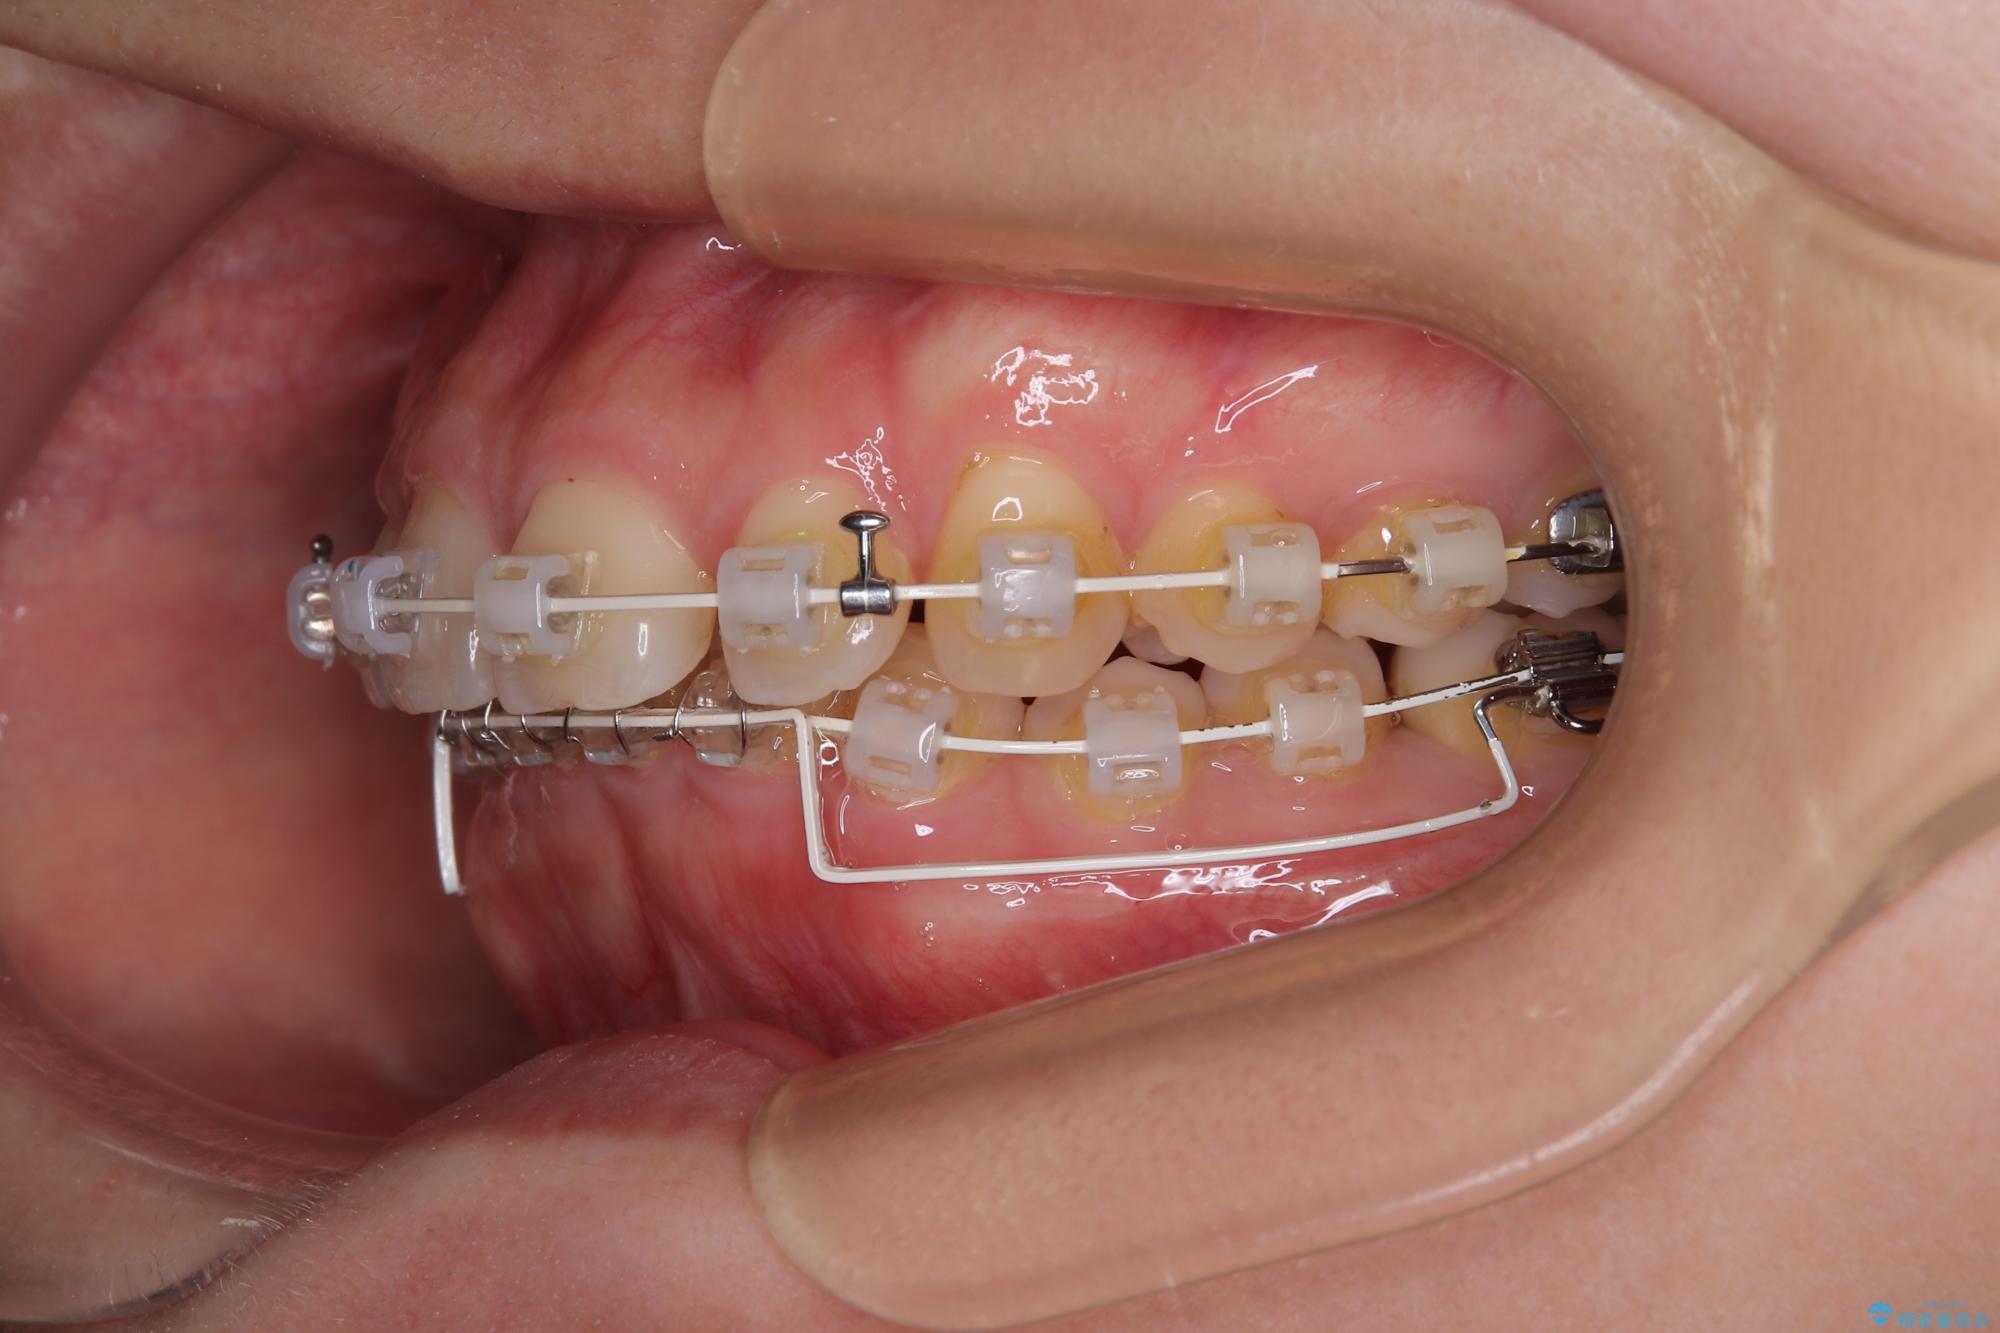

下顎臼歯を起き上がらせるためにユーティリティーアーチを使用し、一気に深い咬み合わせを改善することができました。